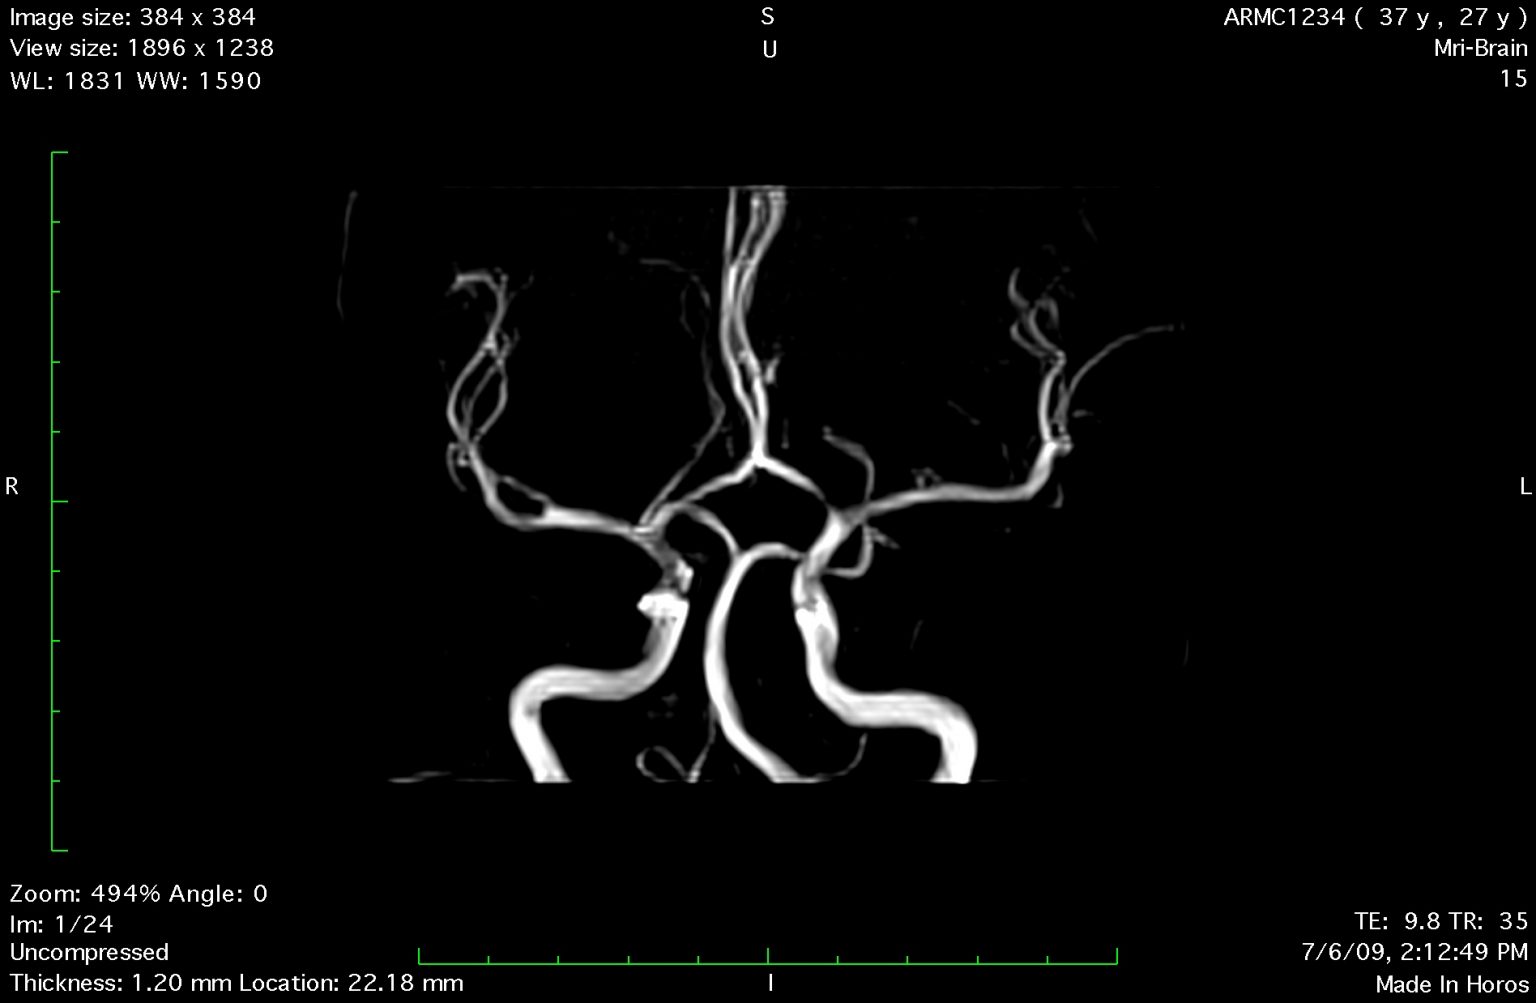

Tích hợp phần mềm: Tự phát triển, hỗ trợ DICOM, PACS, MIP/MPR 3D

Tim mạch, mạch máu